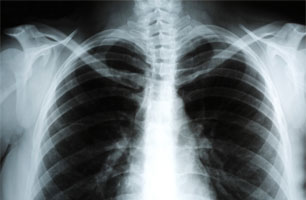

Three common types of mesothelioma form within the human body: pleural, peritoneal, and pericardial. After being inhaled or swallowed, asbestos fibers are able to penetrate and damage different areas within the body. Damaged areas can progress into tumors that ultimately kill the victim.

Diagnosing mesothelioma has been difficult for doctors, mostly because the symptoms so much resemble those of other respiratory diseases. It is not uncommon for a senior citizen to be misdiagnosed with pneumonia, when they are really suffering from pleural mesothelioma.